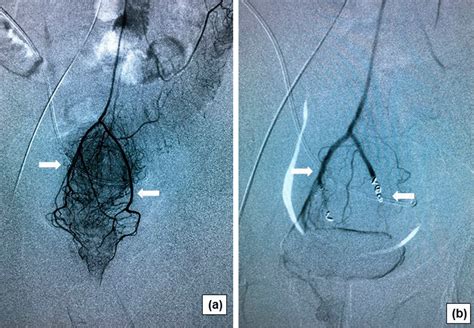

Hemorrhoid Artery Embolization is a cutting-edge, image-guided procedure performed by interventional radiologists. Unlike traditional surgery, which physically removes the hemorrhoidal tissue, HAE works by targeting the blood supply that feeds the hemorrhoids. By reducing the arterial blood flow to the hemorrhoidal plexus, the procedure causes the hemorrhoids to shrink over time, effectively alleviating symptoms like bleeding, pain, and protrusion.

Because it is a minimally invasive technique, it does not require general anesthesia or incisions in the sensitive anal region. Instead, a tiny catheter is guided through a blood vessel in the wrist or groin to the specific arteries supplying the hemorrhoids. Small particles are then injected to block these vessels, successfully reducing the pressure and engorgement of the hemorrhoidal tissues.

3. Embolization: Once the specific hemorrhoidal arteries are identified, specialized embolic agents are injected to reduce the blood supply.